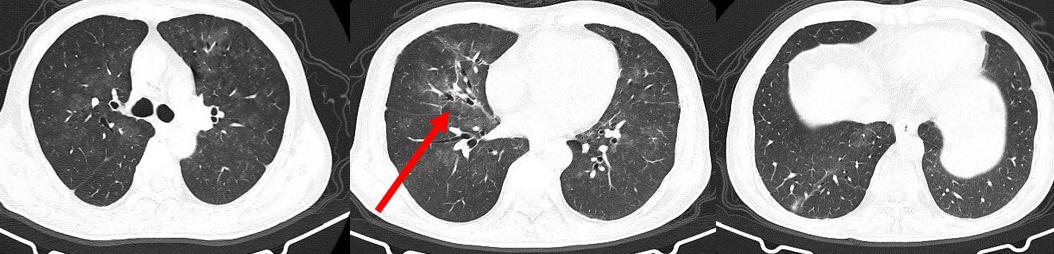

病例: 74岁女性咳嗽咳痰伴气短1月余,已经有亚急性过程了,1月前无明显诱因出现咳嗽,伴喘鸣音,白痰,不易咳出,活动后气短。当地抗感染治疗效果不佳。实验室检查:血常规 WBC 4.52*10^9/L,LY# 0.93*10^9/L,NE% 72.3%。虽然感染指标并不高,但两肺有多发病变。

胸部CT示(12-18):两肺多发斑片絮状影,右中肺及两下肺实变,考虑感染可能。

治疗中患者的氧合指数仍然在快速下降,我们复查CT,显示大部分病变在进展。

图:胸部CT(12-24):两肺纹理增多,两肺门影增浓,两肺野内多发斑片影,较前2021-12-18部分稍有好转,部分稍明显。

仔细比对后,我发现有一个病灶吸收了,机化性肺炎?气管镜下并没有明显感染的征象,后来,NGS只检出纹带棒状杆菌7个序列、光滑念珠菌16个序列,载量很低,而且这两个病原体本身就存在于呼吸道,所以我将它们定义为阴性。

这时进行治疗调整:2021.12.24-12.26:比阿培南0.3g q6h+替加环素 100mg q12h+甲强龙 120mg qd;12.27-2022.01.02:哌拉西林他唑巴坦4.5g q6h+甲强龙 40 mg qd。激素加量、抗生素两天后减量了。治疗效果体现在氧合指数上,患者的氧合指数开始抬头。经过7天的治疗,CT显示所有病灶都在吸收。

图:胸部CT(12-31):两肺野内多发斑片影,较前好转。